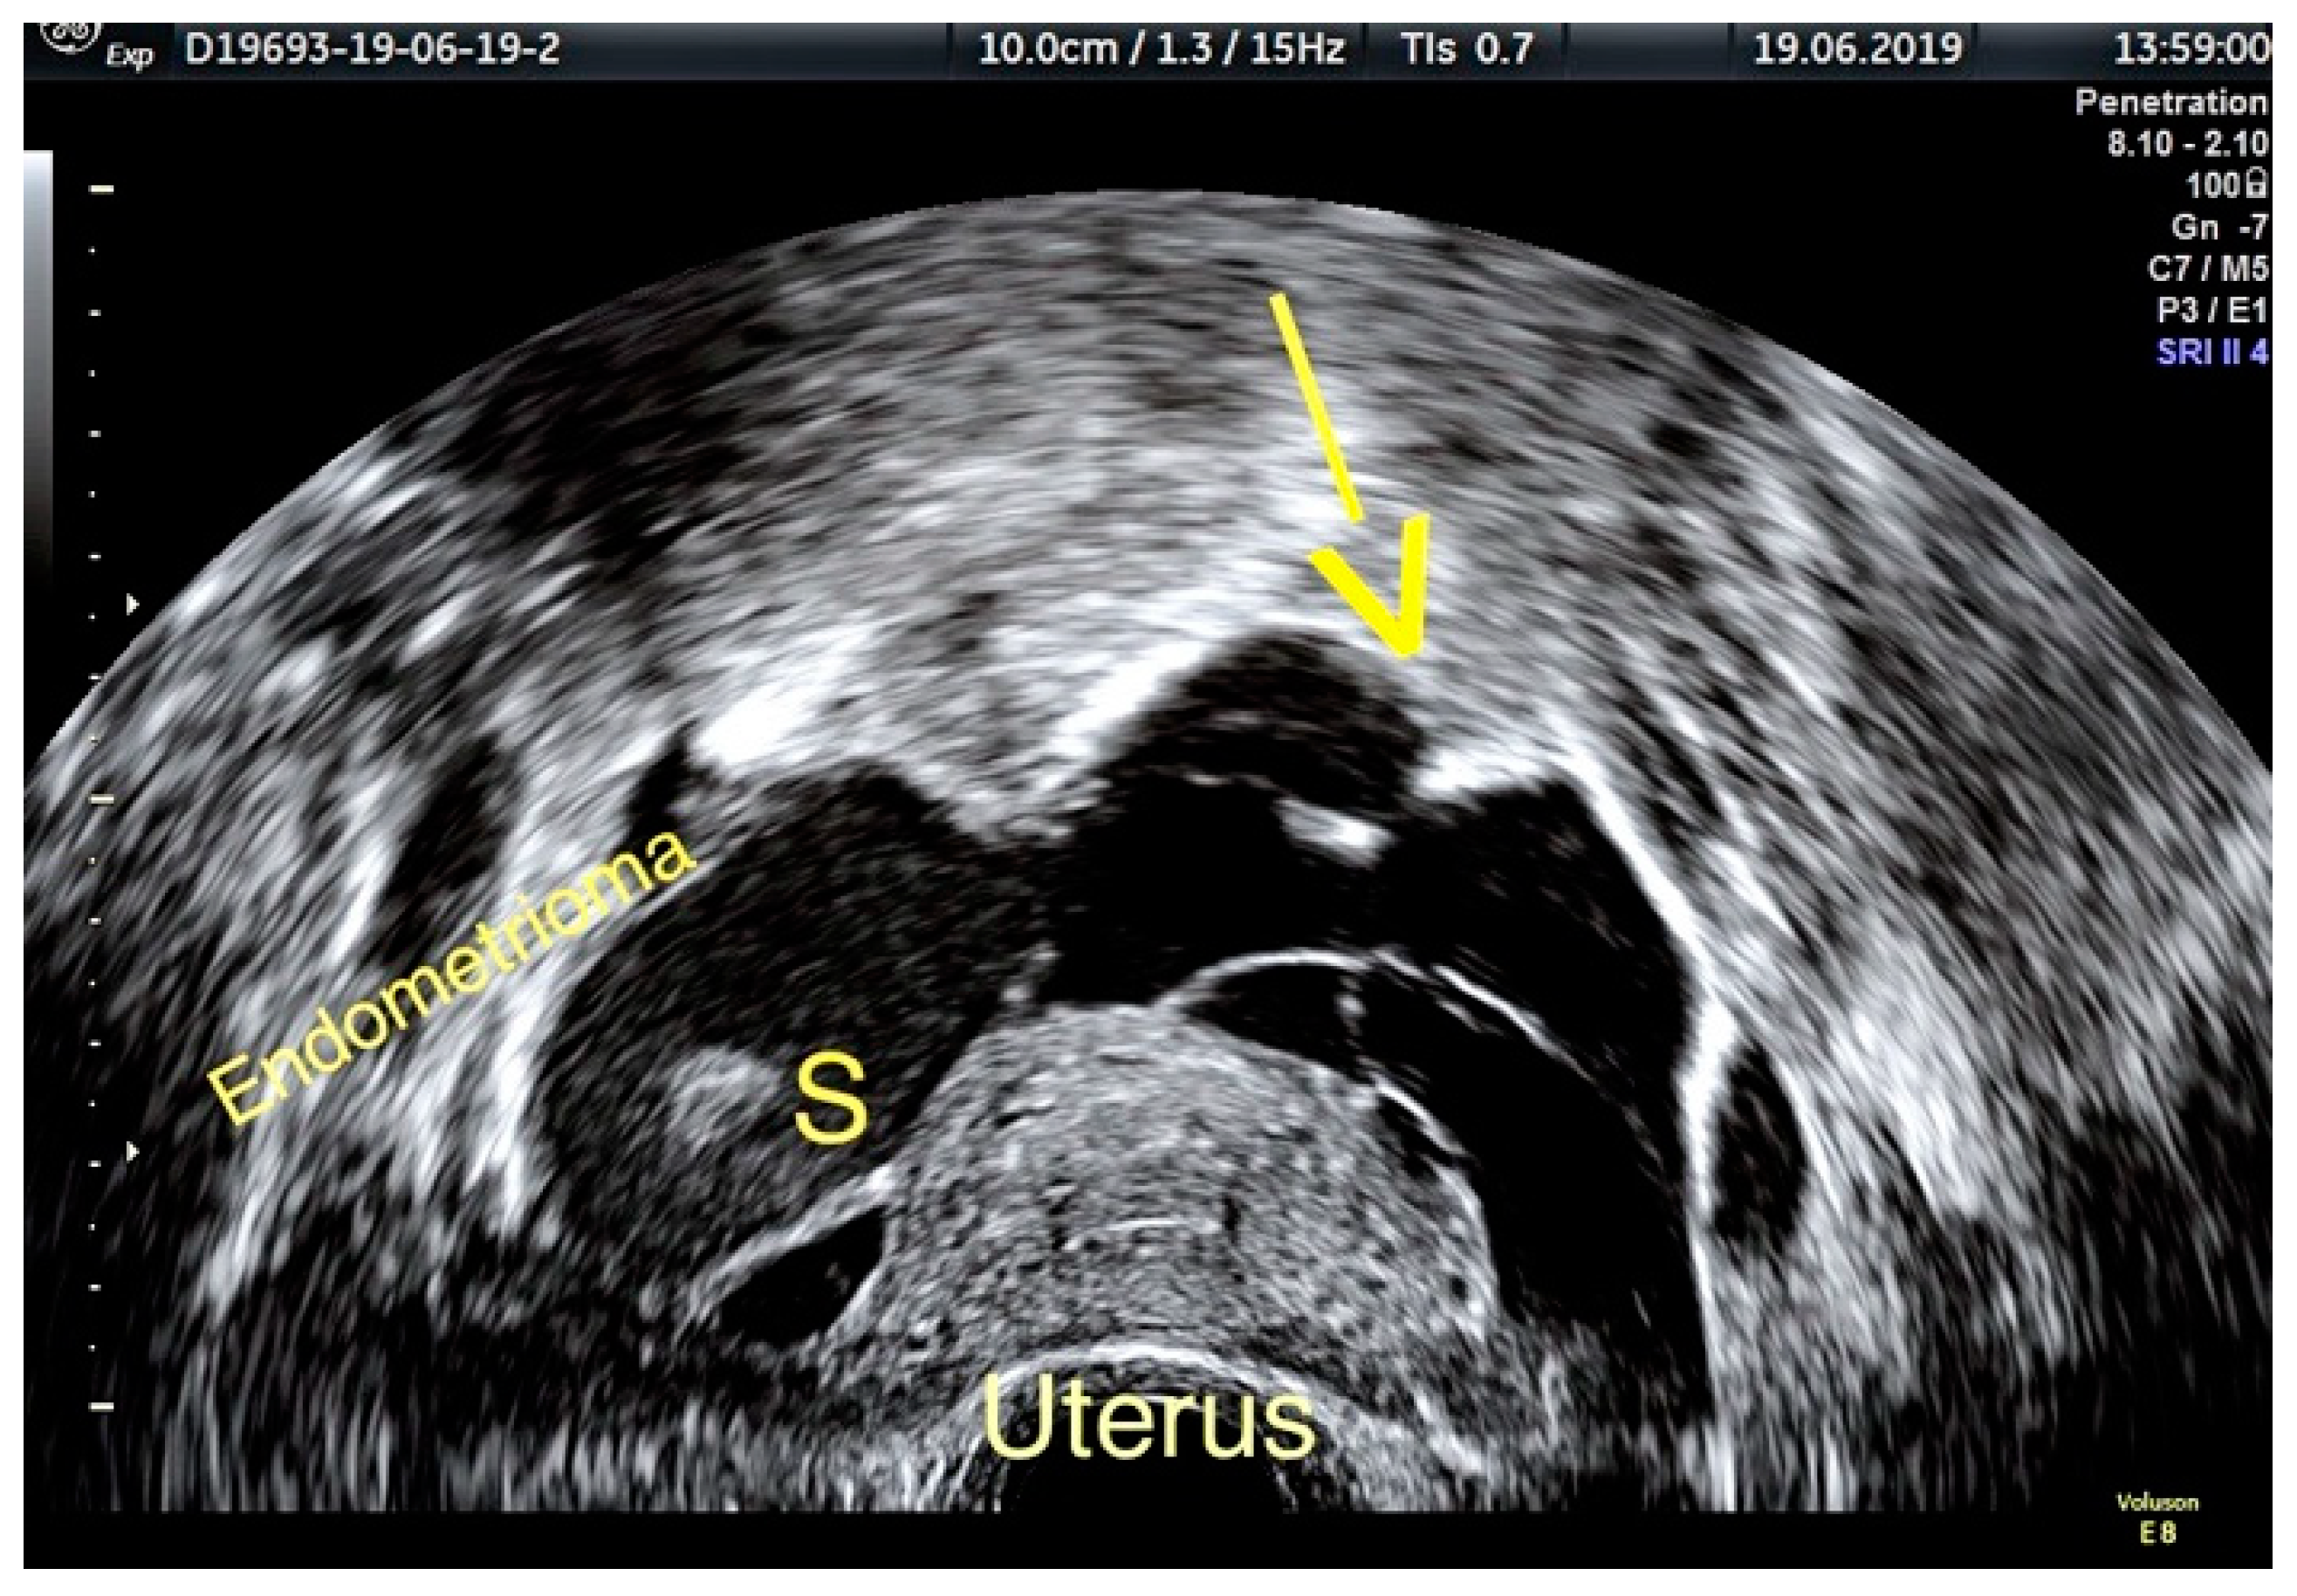

3.1. ADNEXA